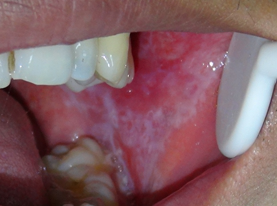

3、白斑

白斑多见于中老年男性,主要症状表现为粗糙、木涩感,伴糜烂时可有刺激痛、自发痛。属于癌前病变。

早期发现、诊断、治疗非常重要,白斑的早期预防是重点,去除刺激因素,局部药物治疗,对有癌变倾向的部位及时手术并活检,定期复查。